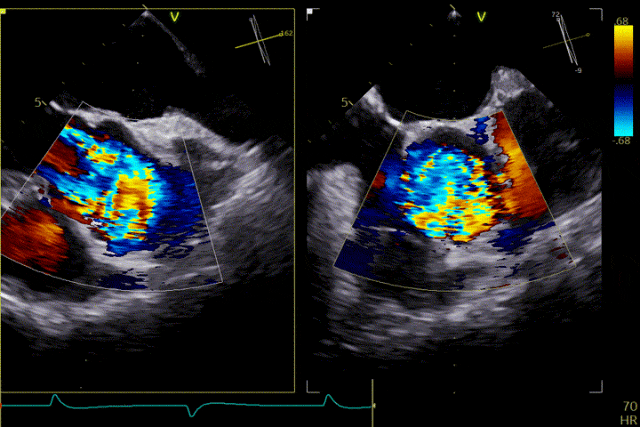

Twenty days ago, he visited the outpatient clinic, where echocardiography indicated aortic valve calcification with severe regurgitation. Recently, the patient again experienced chest tightness and shortness of breath and was admitted for further treatment. His past medical history includes hypertension for 4 years, previous cerebral infarction, and status post cholecystectomy 1 year ago. On admission, the diagnoses were: severe aortic valve insufficiency, grade 3 hypertension (very high risk), and coronary atherosclerotic heart disease.Echocardiography findings showed aortic valve calcification, prolapse of the right coronary cusp with severe insufficiency, increased transvalvular aortic flow velocity, and mild mitral and tricuspid regurgitation. Coronary angiography revealed a normal left main coronary artery, no significant stenosis in the left anterior descending artery, scattered plaques in the circumflex artery, and no significant stenosis in the right coronary artery.

Preoperative Echocardiography

The patient's severe aortic regurgitation was successfully corrected. Postoperatively, there was no residual regurgitation or paravalvular leak. Postoperative echocardiography showed that the bioprosthetic valve had normal opening and closing function, with a mean transvalvular pressure gradient of 2 mmHg and normal flow velocity. The patient demonstrated good recovery, with a significant improvement in cardiac function compared with the preoperative status.